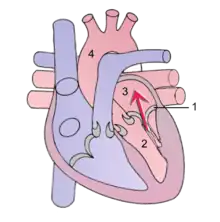

| Mitral regurgitation (schematic drawing) During systole, contraction of the left ventricle causes abnormal backflow (arrow) into the left atrium. 1 Mitral valve 2 Left ventricle 3 Left atrium 4 Aorta | |

Mitral regurgitation (MR), also known as mitral insufficiency or mitral incompetence, is a form of valvular heart disease in which the mitral valve is insufficient and does not close properly when the heart pumps out blood.[3][4][5] It is the abnormal leaking of blood backwards – regurgitation from the left ventricle, through the mitral valve, into the left atrium, when the left ventricle contracts.[4] Mitral regurgitation is the most common form of valvular heart disease.[3]

Mitral regurgitation, also known as mitral insufficiency or mitral incompetence, is the backward flow of blood from the left ventricle, through the mitral valve, and into the left atrium, when the left ventricle contracts, resulting in a systolic murmur radiating to the left armpit.[5][3]